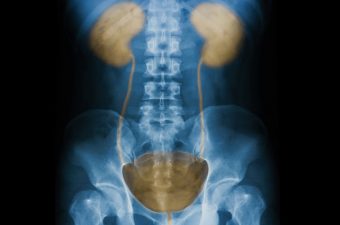

A imagem ao lado mostra a anatomia do trato urinário inferior da mulher. Repare como a vagina e a entrada da uretra na mulher ficam muito próximas do ânus. A saída da uretra feminina fica muito mais próxima do ânus do que a masculina. Além disso, a uretra do homem é mais extensa, fazendo com que a E.coli tenha que percorrer um caminho maior até chegar à bexiga.

Isto significa que anatomicamente é muito mais fácil para as bactérias vindas do ânus alcançarem a bexiga da mulher do que a bexiga do homem. Portanto, a anatomia geniturinária explica o porquê das mulheres terem cistite com frequência e os homens não.